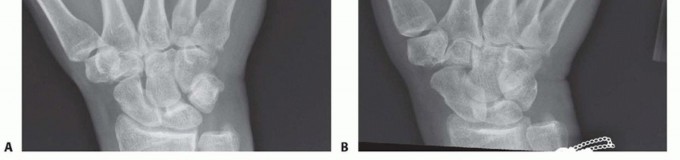

FIG 5 • A. Missing fourth metacarpal shaft and base after gunshot wound. Patient had tenuous dorsal skin. Metacarpal head temporarily stabilized with buried pins from fifth metacarpal. B. Once the soft tissues stabilized, the metacarpal was grafted from the iliac crest and stabilized with plate and screws to the hamate. C. Dorsal sensory branch of the ulnar nerve travelling through the center of the wound on a different patient. Grossly contaminated wounds, or those with tenuous soft tissues, may be best managed initially with limited fixation until more definitive fixation can be performed (FIG 5A).Bone grafting may also need to wait until the soft tissues have stabilized (FIG 5B).The need to address nerve, vessel, or tendon injuries may also affect the approach (FIG 5C).